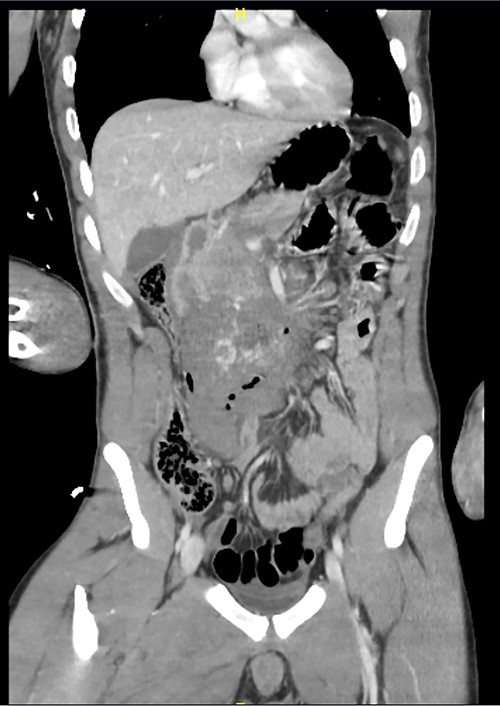

Here, we report a case of a 21-year-old man who was admitted to our hospital following a motor vehicle collision where he was a pedestrian, hit by a car and pushed against the bumper of another car. Upon arrival to the hospital, he was conscious and oriented, with normal vital signs. Abdominal examination revealed ecchymosis over the epigastric area with tenderness, however, no distention was noticed. Focused assessment with sonography for trauma result was positive in the right upper quadrant. His initial blood test results revealed a white blood cell (WBC) count of 26.5 × 109 cells/l and a hemoglobin level of 150 g/l. His serum amylase and lactic acid levels were 92 U/l and 4.53 mmol/l, respectively. His base deficit was 4.3. He underwent abdominal computed tomography (CT) with oral contrast, which showed query duodenal and possible pancreatic transection with active arterial extravasation (Figs 1–3). In addition, CT revealed a comminuted right intertrochanteric femoral fracture without associated vascular injury.

Despite its limitations in distinguishing between duodenal hematoma and duodenal perforation, CT with intravenous and intraluminal contrast remains the gold standard diagnostic test in stable patients with blunt abdominal trauma [1]. In the reported case, CT revealed duodenal and possible pancreatic transection with active arterial extravasation.